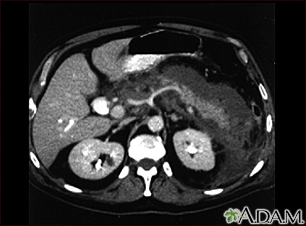

Pancreatitis, acute - CT scanBackPancreatitis, acute - CT scanThis upper abdominal CT scan shows inflammation and swelling of the pancreas caused by acute infection (pancreatitis). E-mail FormEmail ResultsName:Email address:Recipients Name:Recipients address:Message: